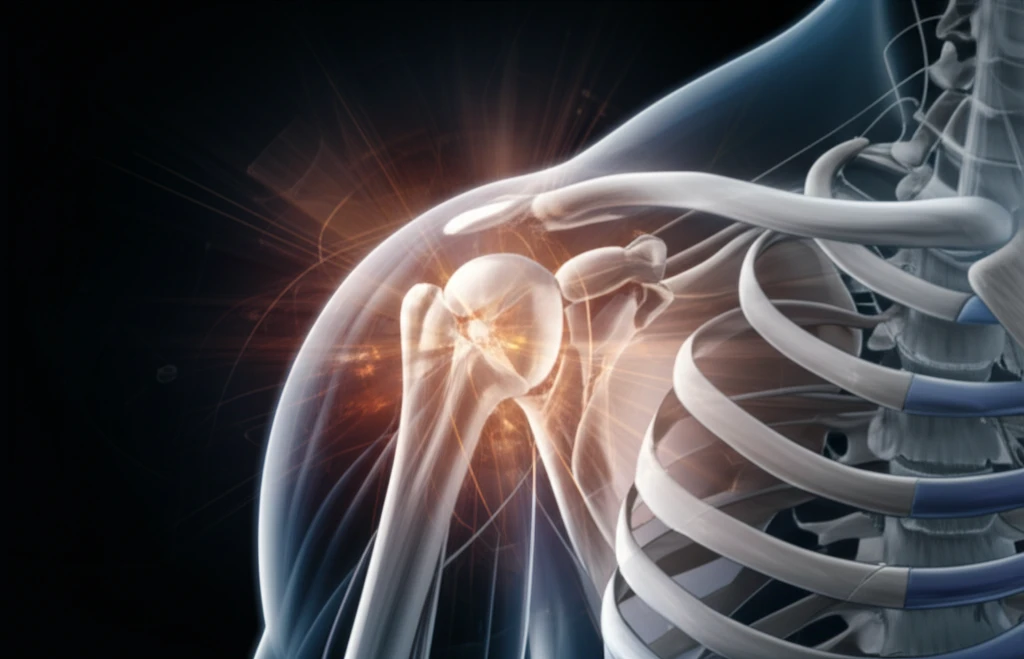

Shoulder pain ranks among the most common musculoskeletal complaints, significantly impacting daily life and occupational performance. Shoulder impingement syndrome (SIS), a prevalent condition, accounts for a substantial portion of these cases, with diagnoses ranging from 44% to 65% of all shoulder pathologies. This condition not only affects athletes but also individuals engaged in repetitive overhead activities, making effective management crucial.

Despite its widespread occurrence, the effectiveness of physiotherapy in treating SIS remains a topic of ongoing debate. Characterized by pain, limited range of motion, and impaired function, SIS often leads to decreased quality of life and work productivity. Understanding the role of physiotherapy in managing SIS is essential for healthcare professionals and individuals seeking relief from this debilitating condition.

Shoulder impingement syndrome occurs when the tendons of the rotator cuff muscles become compressed and irritated as they pass through the subacromial space. This compression can lead to inflammation, pain, and restricted movement. The condition typically affects individuals in their fourth and fifth decades of life and is more commonly seen in women. Factors contributing to SIS include: